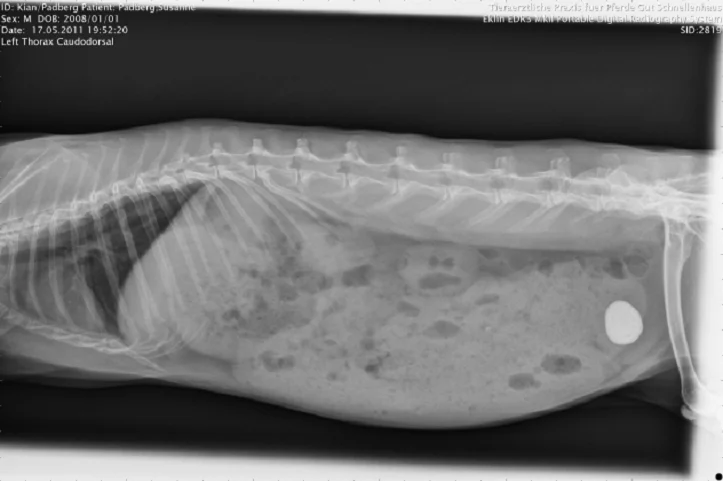

Рентгенография брюшной полости

- Уролиты оксалата кальция рентгенконтрастны и обычно обнаруживаются при обзорной рентгенографии. Уролиты должны быть дифференцированы от осадка в мочевом пузыре. УЗИ диагностика мочевого пузыря и пальпация могут быть полезны, чтобы отличить одиночные уролиты от аморфного песка;

- Иногда относительно крупные уролиты могут быть обнаружены в мочеиспускательном канале, вызывая только частичную непроходимость;

- Камни можно обнаружить и в почках или мочеточниках.